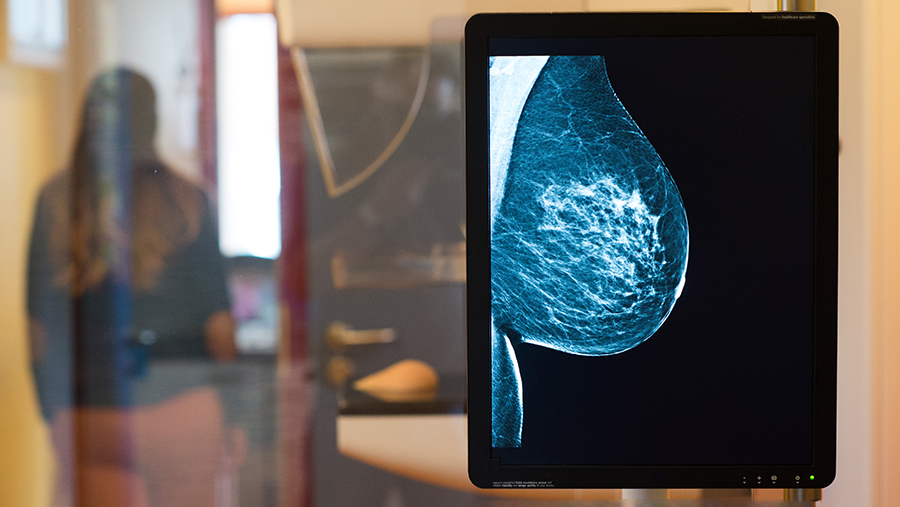

Photo: TASS/Klaus-Dietmar Gabbert